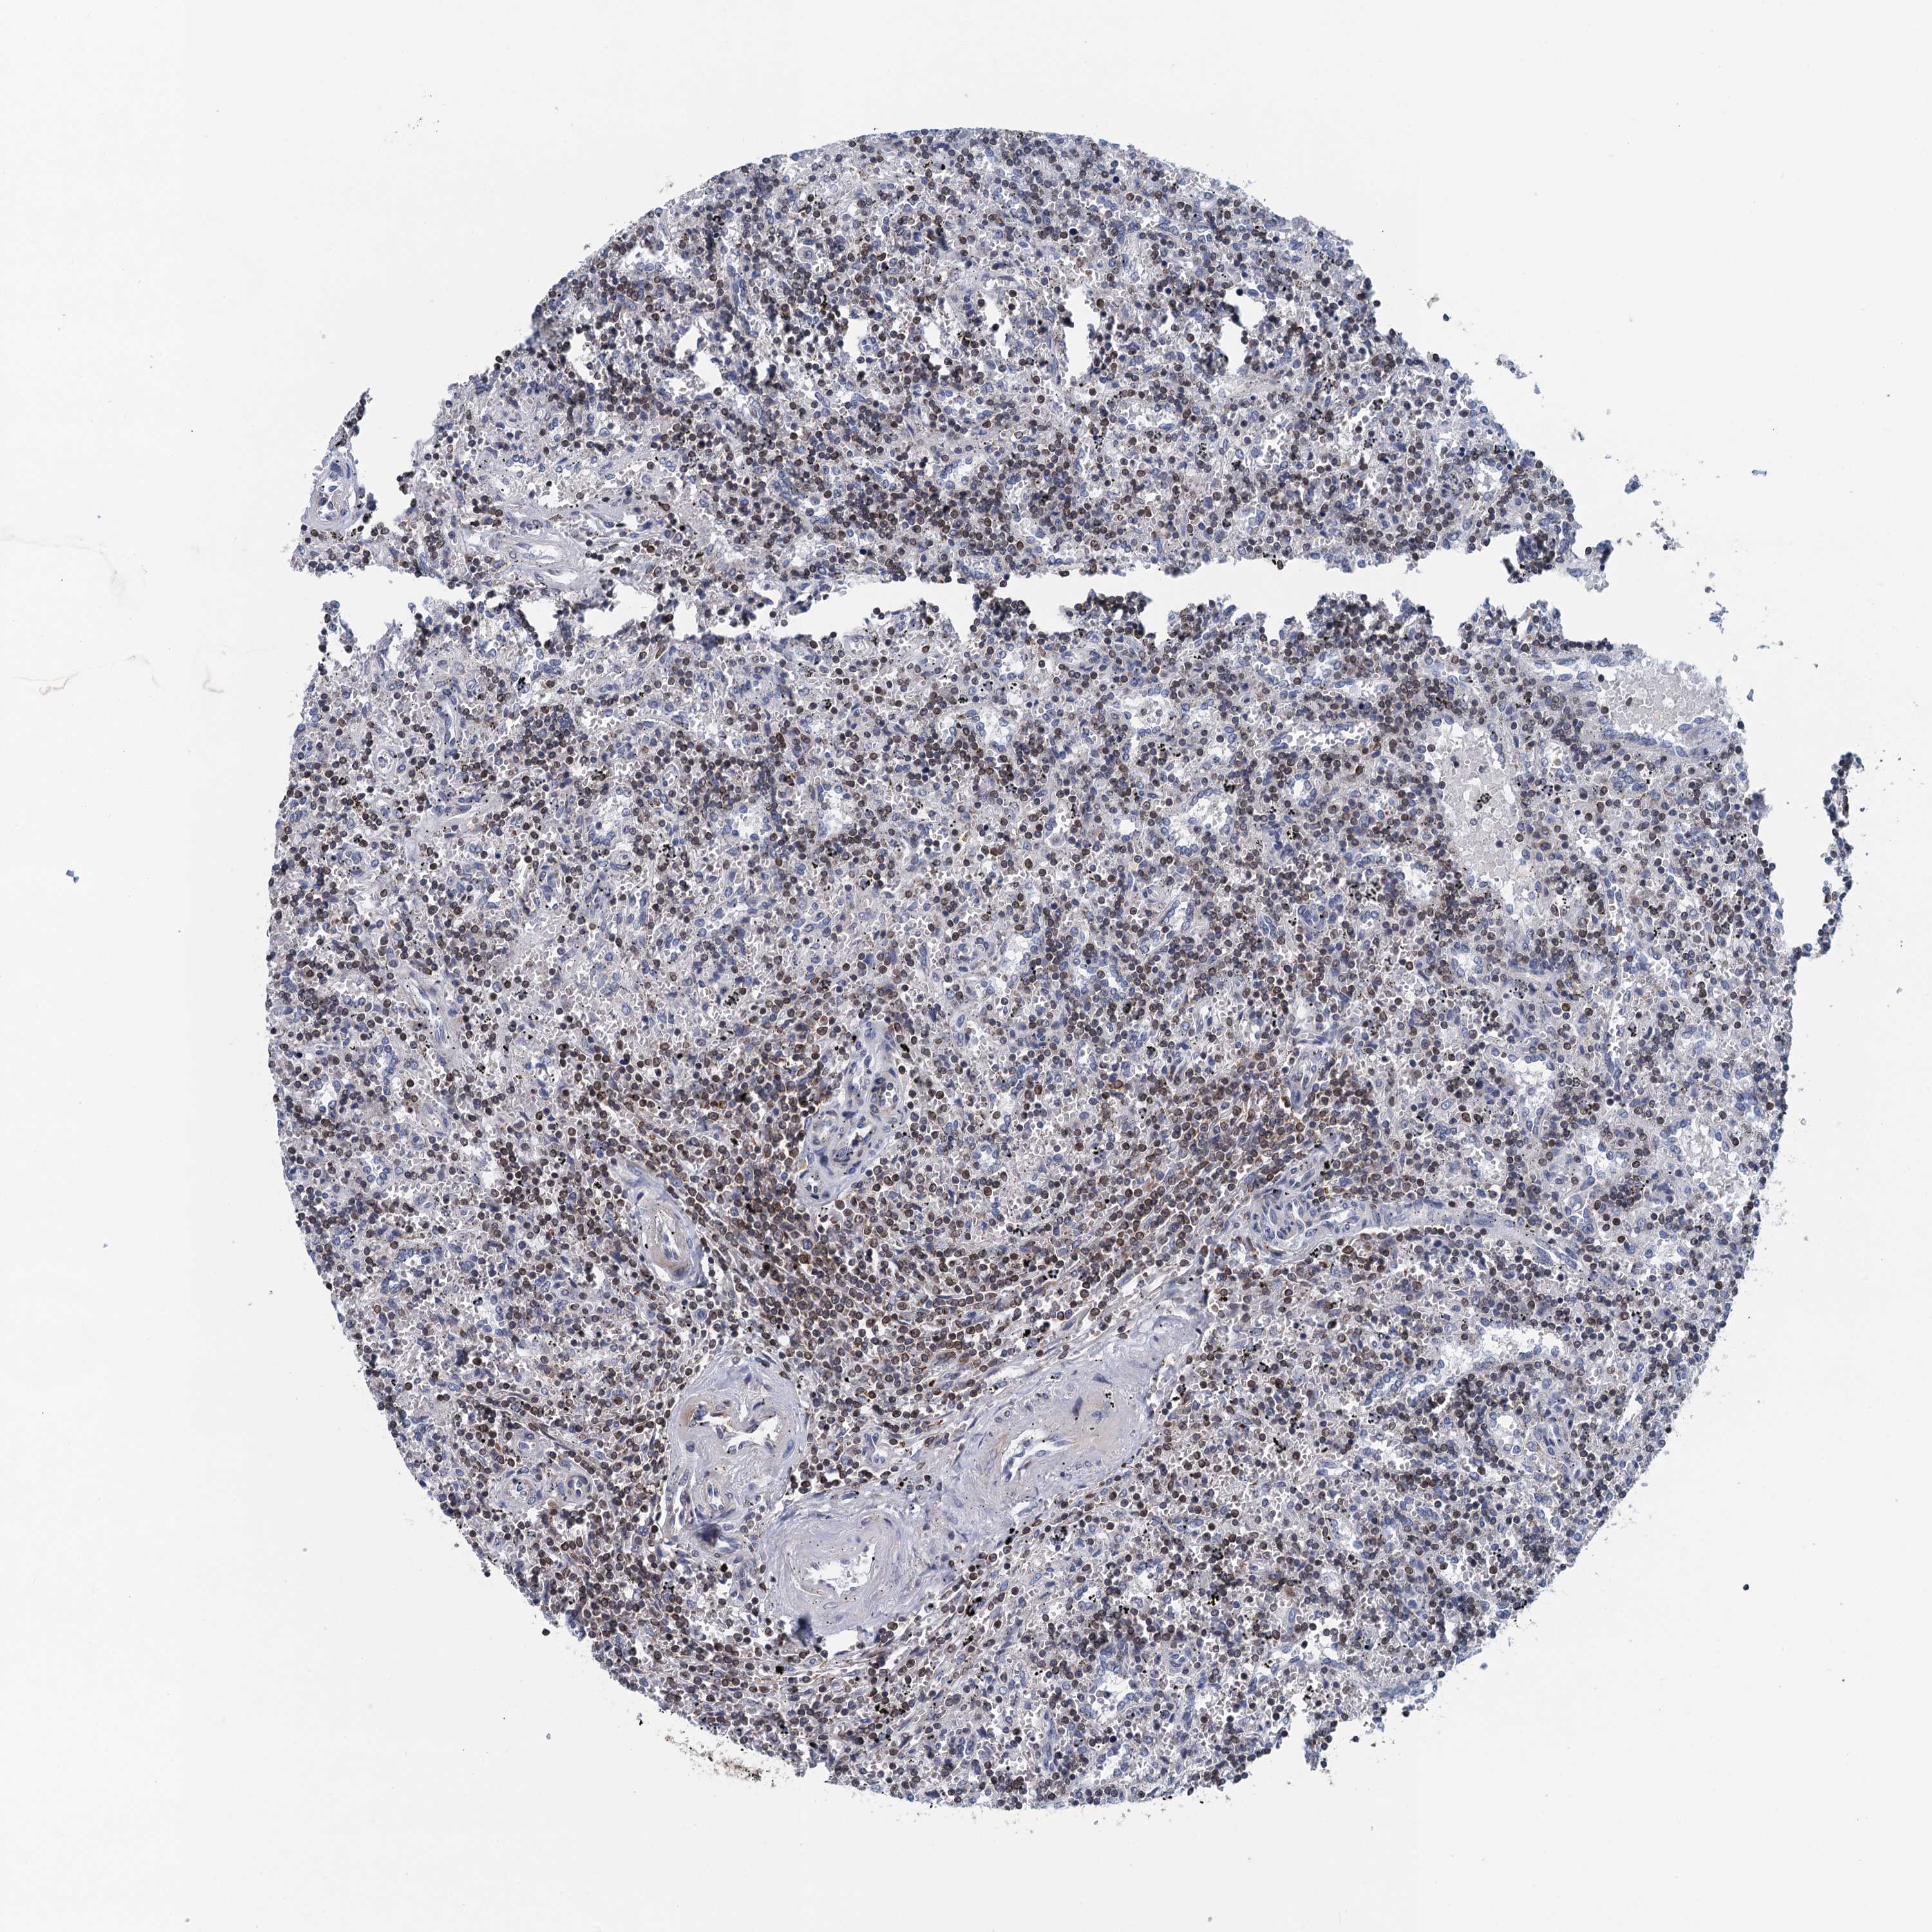

CANCER LYMPHOMA Show tissue menu

LYMPHOMA - Protein expressioni

A mouse-over function shows sample information and annotation data. Click on an image to view it in a full screen mode. Samples can be filtered based on level of antibody staining by selecting one or several of the following categories: high, medium, low and not detected. The assay and annotation is described here.

Each image is clickable and will lead to virtual microscopy that enables deeper exploration of all samples and also displays staining intensity scores, fraction scores and subcellular localization as well as patient and tissue information for each sample.

Antibody HPA040796

Staining

High

Medium

Low

Not detected

Intensity

Strong

Moderate

Weak

Negative

Quantity

>75%

75%-25%

<25%

None

Location

Nuclear

Cytoplasmic/membranous

Cytoplasmic/membranous,nuclear

Hodgkin's disease, NOS

Malignant lymphoma, non-Hodgkin's type, High grade

Malignant lymphoma, non-Hodgkin's type, Low grade